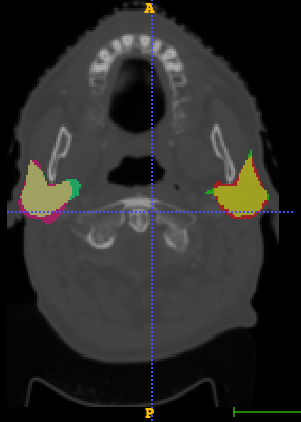

In Chapter 6, we propose an end-to-end, atlas-free 3D convolutional deep learning framework for fast and fully automated whole-volume HaN anatomy segmentation [115]. Our deep learning model, called AnatomyNet, segments OARs from head and neck CT images in an end-to-end fashion, receiving whole-volume HaN CT images as input and generating masks of all OARs of interest in one shot. AnatomyNet is built upon the popular 3D U-net architecture, but extends it in three important ways: 1) a new encoding scheme to allow auto-segmentation on whole-volume CT images instead of local patches or subsets of slices, 2) incorporating 3D squeeze-and-excitation residual blocks in encoding layers for better feature representation, and 3) a new loss function combining Dice scores and focal loss to facilitate the training of the neural model. These features are designed to address two main challenges in deep-learning-based HaN segmentation: a) segmenting small anatomies (i.e., optic chiasm and optic nerves) occupying only a few slices, and b) training with inconsistent data annotations with missing ground truth for some anatomical structures. We collect 261 HaN CT images to train AnatomyNet, and use MICCAI Head and Neck Auto Segmentation Challenge 2015 as a benchmark dataset to evaluate the performance of AnatomyNet. The objective is to segment nine anatomies: brain stem, chiasm, mandible, optic nerve left, optic nerve right, parotid gland left, parotid gland right, submandibular gland left, and submandibular gland right. Compared to previous state-of-the-art results from the MICCAI 2015 competition, AnatomyNet increases Dice similarity coefficient by 3.3% on average. AnatomyNet takes about 0.12 seconds to fully segment a head and neck CT image of dimension , significantly faster than previous methods. In addition, the model is able to process whole-volume CT images and delineate all OARs in one pass, requiring little pre- or post-processing. We demonstrate that our proposed model can improve segmentation accuracy and simplify the auto-segmentation pipeline. These contributions are released as an open-source software package called AnatomyNet, which is publicly available555https://github.com/wentaozhu/AnatomyNet-for-anatomical-segmentation. Portions of this chapter were published as part of [115].

- [121] W. Zhu and X. Xie. Adversarial deep structural networks for mammographic mass segmentation. arXiv:1612.05970, 2016.